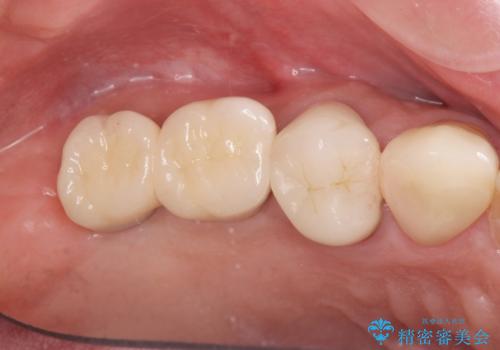

人工歯根であるインプラントを埋入することで奥歯でまたしっかりと噛める咬合機能を回復します。

- 88万円(インプラント×2・仮歯×2・チタンカスタムアバットメント×2・ジルコニアクラウン×2)費用は治療当時の料金となります

またしっかりと噛めるようになり、食事を楽しめるようになった!と喜んでいただくことができました。